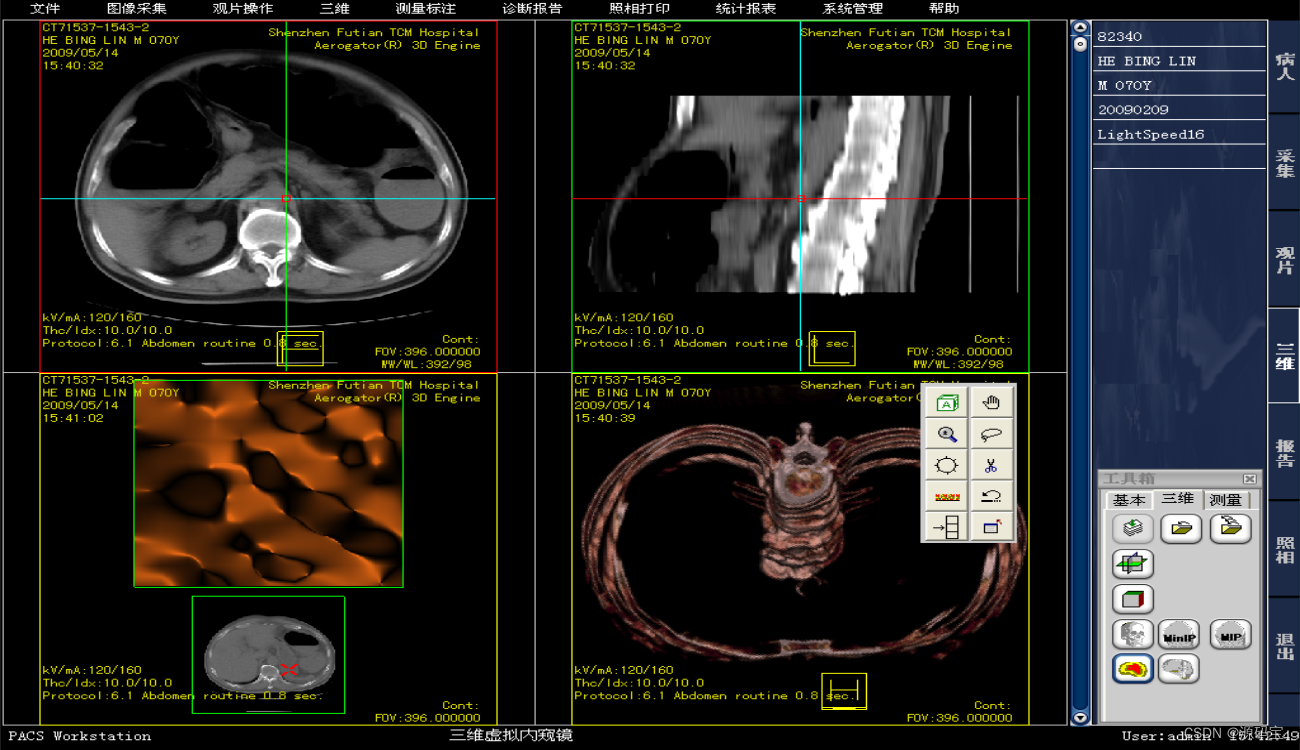

三甲医院医学影像PACS系统源码,集成三维影像后处理功能,包括三维多平面重建、三维容积重建、三维表面重建、三维虚拟内窥镜、最大/小密度投影、心脏动脉钙化分析等功能。系统功能强大,代码完整。

集成三维影像后处理功能。

(7)图像后处理与重建

MPR\CPR(三维多平面重建)

VRT(三维容积重建)

SSD(三维表面重建)

VE(虚拟内窥镜)

MIP(最大密度投影)、MinIP(最小密度投影)

CalSCore(心脏图像冠脉钙化积分)